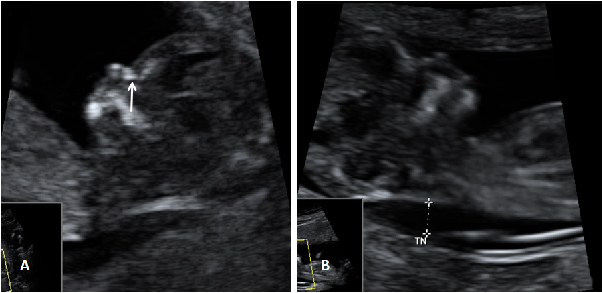

La ecografía en tres dimensiones muestra un feto de 13 semanas de gestación con el cordón umbilical alrededor del cuello. En la imagen rotatoria se puede observar la situación del cordón, que sube por el tórax y que seguramente puede causar complicaciones en el embarazo.